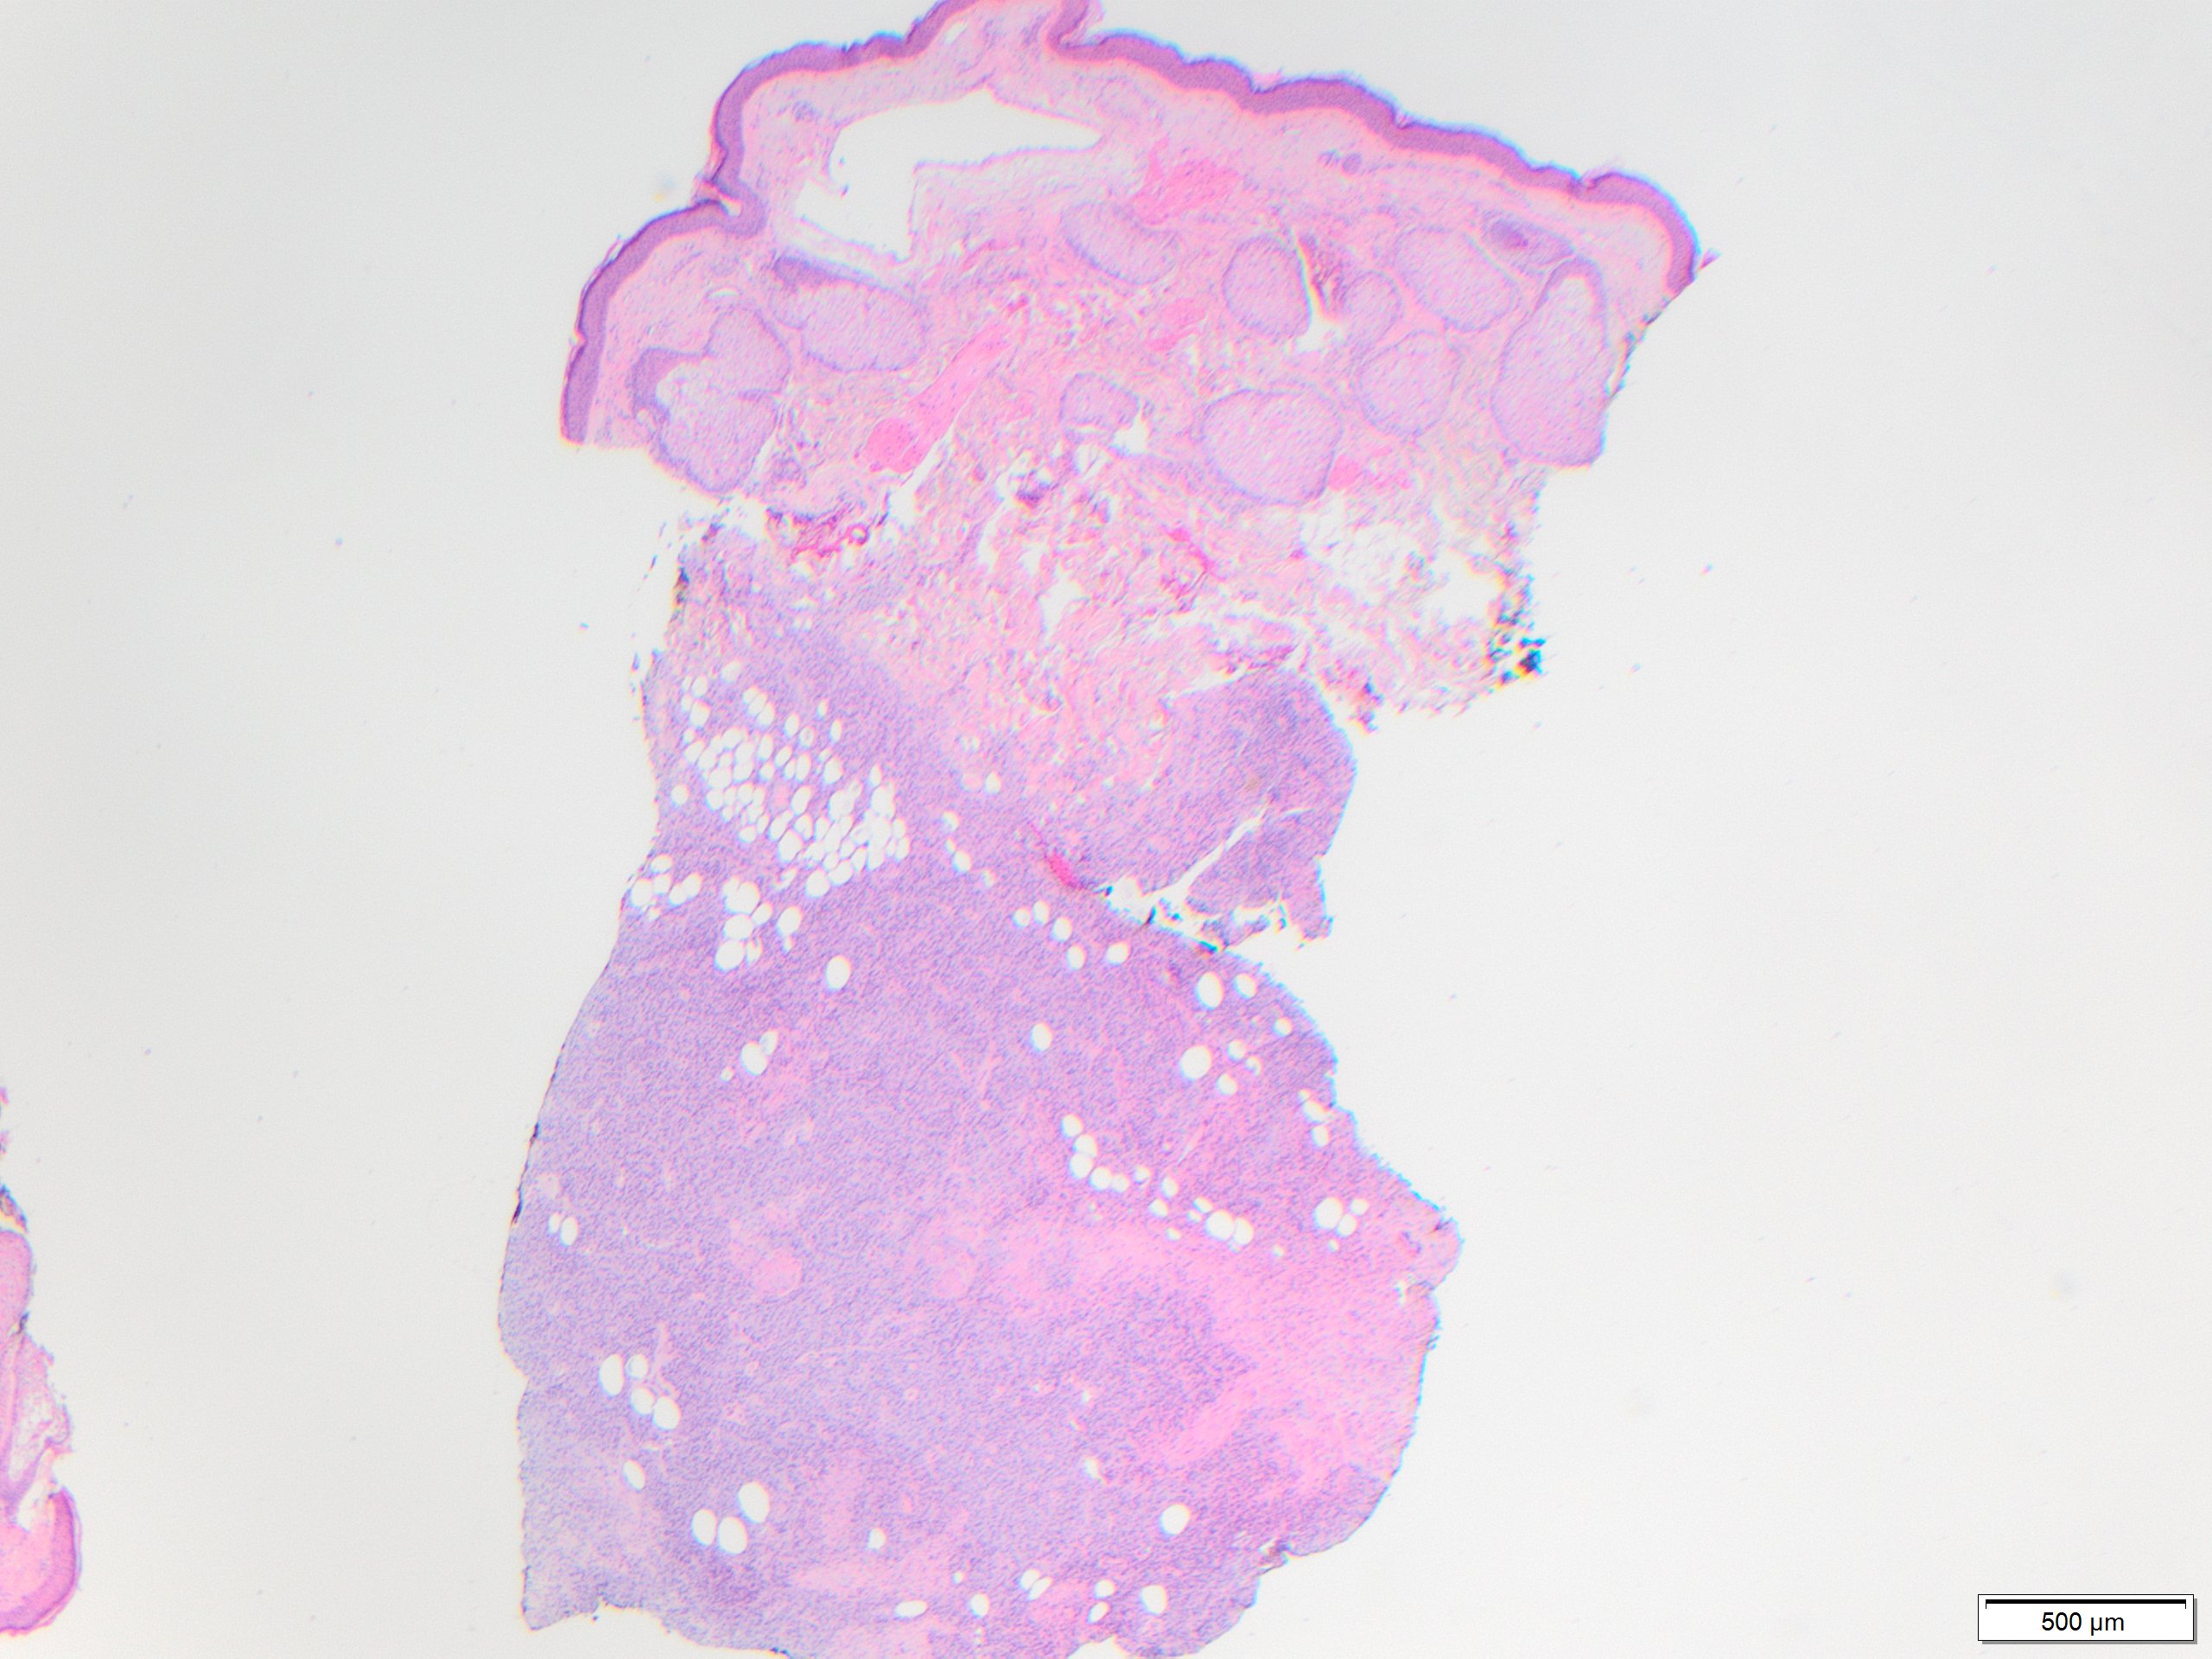

In early stage DFSP forms as a firm plaque-like lesion that grows slowly and later becomes nodular, hence “protuberant”. Most DFSP are biopsied during the nodular stage, consisting of a solitary-protuberant gray-mass involving subcutis and skin. Some tumors may be centered in the subcutaneous soft tissue with subtle dermal involvement. Therefore, involvement of the dermis may not always be evident in the initial biopsy, as seen in the present case.

While these tumors may appear grossly circumscribed, microscopically DFSP are ill-defined with diffuse infiltration of dermis and subcutis. The tumor is composed of uniform spindled cells with collagenous stroma, often arranged in a storiform or “cartwheel” pattern, with infiltration of fat lobules and adnexal structures at the periphery. Some DFSP lack the collagenous storiform arrangement and instead display variably myxoid stroma, and some DFSP, like this example, may display myoid differentiation and so called “myoid-bodies” which may also be seen in other types of mesenchymal tumors. By immunohistochemistry DFSP are diffusely positive for CD34, and negative for S100, smooth muscle actin (SMA) and desmin, except myoid areas when present, are positive for SMA. Areas with herringbone architecture and loss of CD34 staining, may indicate fibrosarcomatous transformation. The histologic differential diagnosis of DFSP includes benign fibrous histiocytoma, neurofibroma, plaque-like CD34-positive dermal fibroma, and superficial acral fibromyxoma.